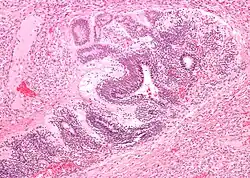

| Micrograph of the primitive neuroepithelium of an immature teratoma of the mediastinum. H&E stain. | |

Germ cell tumors comprise 15% of mediastinal masses and usually affect young adult men between the ages of 18 and 29. These are rare tumors that develop from reproductive cells that grow in the chest instead of the gonads during early development. These tumors resemble testicular germ cell tumors and are classified into three types: teratomas, seminomas, and non-seminomatous tumors such as yolk sac tumors or embryonal carcinomas[11]. Teratomas are the most common type to form in the mediastinum.

Tumors are initially asymptomatic but may cause chest pain, cough, or shortness of breath when the size causes compression on surrounding structures. The tumor is diagnosed by CT and MRI scans as well as blood markers like AFP, β-hCG and LDH that help classify the type of germ cell tumor.[11] Most teratomas are benign tumors but require close follow-up and treatment. Teratomas are associated with Klinefelter syndrome.Teratomas are usually noncancerous and treated with surgery, while seminomas and non-seminomatous tumors are more aggressive and treated with chemotherapy and surgery.[12] The outlook depends on the tumor classification, with seminomas and teratomas having excellent prognosis and non-seminomatous tumors having a higher chance of metastasis.[13]